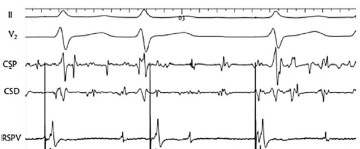

Um engenheiro de 61 anos foi submetido a ablação de fibrilação atrial (FA) paroxística. Os eletrogramas abaixo mostram a leitura dos potenciais elétricos durante ritmo fibrilatório, através de cateter localizado no seio coronário, e a estimulação atrial concomitante através de cateter localizado na veia pulmonar superior direita (VPSD) para avaliar o isolamento da veia pulmonar.

Na imagem acima, II e V2 representam derivações do eletrocardiograma de superfície.

CSP = Seio coronário proximal

CSD = Seio coronário distal (RSPV) = Veia pulmonar superior direita

O que podemos concluir a respeito do isolamento elétrico da veia pulmonar avaliada?